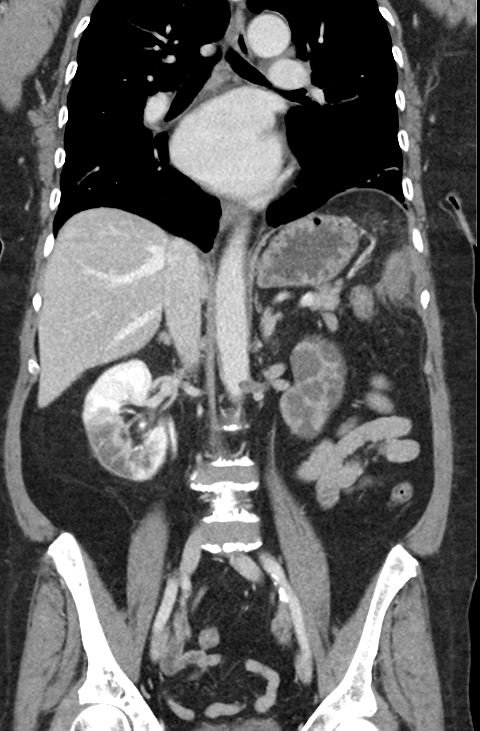

Renal and Splenic Infarcts

A 61-year-old, diabetic, hypertensive woman presented to the emergency department in rapid atrial fibrillation with excruciating, non-tender, left upper quadrant and flank pain. She ran out of her anticoagulant a month before which she had been prescribed after a stroke earlier in the year.

On the coronal sections of computed tomography (CT), bilateral renal infarctions (blue arrows) and several splenic infarctions (green arrows) are noted. Of particular interest, part of the clot totally occluding the left renal artery visibly extends into the aorta (red arrow). The vascular reconstruction image is remarkable for the absent left kidney, the unusual contour of the right kidney and the abnormal splenic blush.

Classic emergency medicine teaching dictates that when a patient with atrial fibrillation has abdominal pain “out of proportion” to the examination, one must consider mesenteric ischemia. Although the bowels clearly carry the highest embolic risk for abdominal viscera, other organs are at risk as well. This case illustrates a rare constellation of segmental splenic infarcts and bilateral renal infarction, with complete left renal artery occlusion stemming from multiple emboli.

Renal infarctions are difficult to predict because symptoms overlap with other potential etiologies such as abdominal aortic aneurysm, nephrolithiasis, mesenteric ischemia, appendicitis, and urinary tract infection.1 Patients with these infarctions typically have complaints such as flank or abdominal pain, nausea, vomiting, and sometimes fever.2 Splenic emboli produce similar nonspecific left-sided symptoms.The index of suspicion may be increased if the patient’s underlying disease state includes embolic risk factors such as atrial fibrillation, ischemic heart disease, infective endocarditis, cardiomyopathy, or valvular disease.3 The key to diagnosis in the emergency department is a CT scan with contrast, which has a sensitivity of over 95% in renal infarction cases.4

Due to the rarity of splenic and renal embolic infarctions, a standard treatment protocol has not been developed.2 Treatment may include anticoagulation, thrombolysis, surgical management, or interventional radiology.5 Our patient had the left renal artery clot extracted by the interventional radiologist followed by anticoagulation.